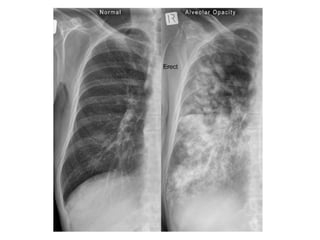

Alveolar Shadows

Air-space (Acinar/alveolar) pattern

• When distal airways and alveoli are filled with

fluid, whether it is a transudate, exudate or

blood, acinus forms a nodular 4-8mm shadow.

• These coalesce into fluffy ill-defined round or

irregular cotton-wool shadows.

• Non-segmental, homogenous or patchy, but

frequently well defined adjacent to fissures.

Cont…

• Vascular markings usually obscured locally.

• Air bronchogram and silhouette sign are

characteristic

• Ground-glass appearance of generalised

homogenous haze with a “bat’s wing” or

“butterfly” perihilar distribution may be seen,

sparing the peripheral lungs.

Pulmonary Edema

• Produces air space opacities with variable

distribution.

• Sparing of the apices and extreme lung bases.

• “Butterfly” or “Bat wings” distribution – central

lungs affected more.

• With progression – opacities coalesce to form a

“white-out” on chest radiograph.

• Blurring of blood vessels occurs.

• Air bronchogram – indicating intra alveolar

edema.